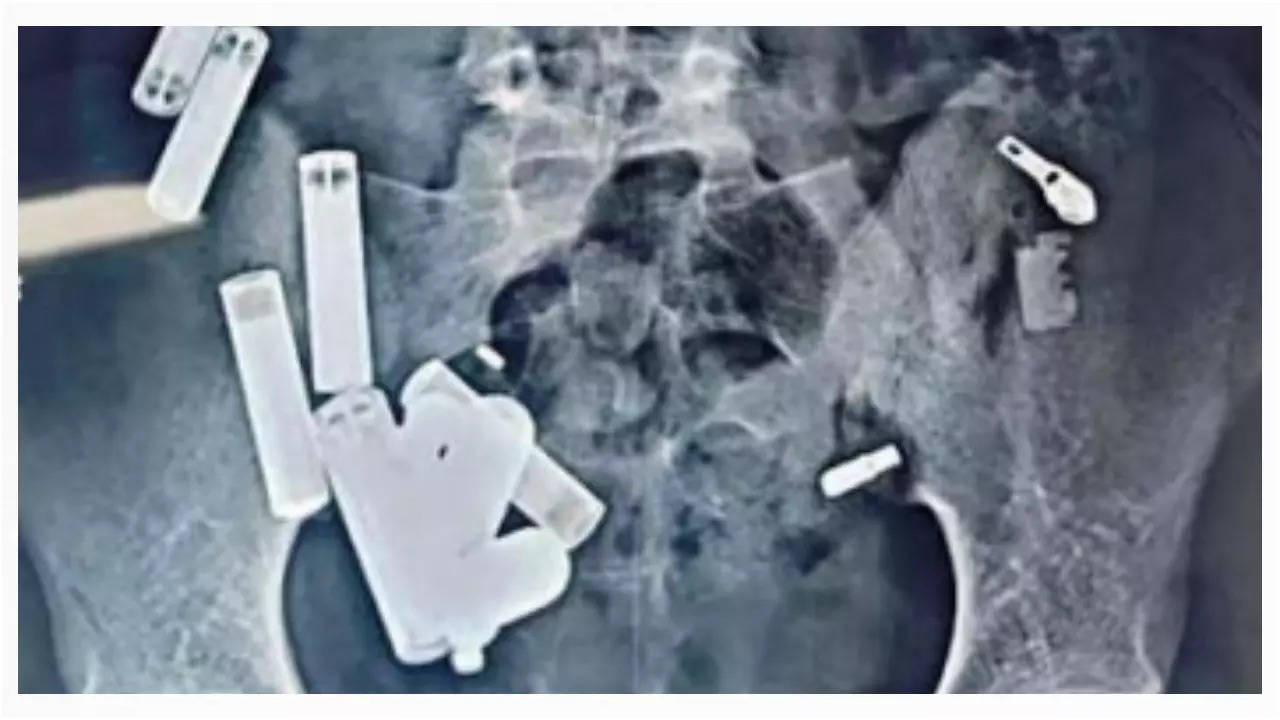

Batteries, chains, screws: 65 objects in stomach kill 14-year-old Hathras boy

A 14-year-old boy from Hathras, UP, died after doctors at Delhi’s Safdarjung Hospital removed 65 objects from his stomach, including…